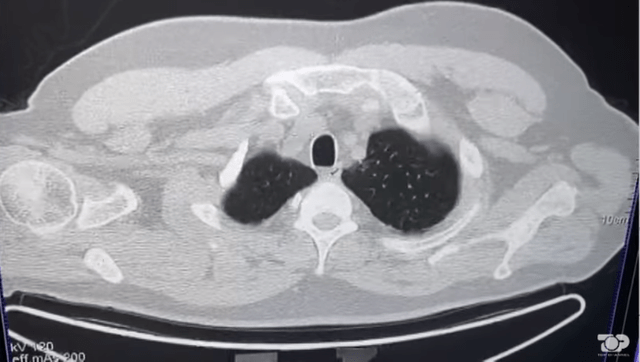

Nëse për pacientët të cilët e kanë kaluar lehtë virusin është e mjaftueshme një vizitë te mjeku i përgjithshëm, individët që kanë pasur formë mesatare ose të rëndë të sëmundjes, apo kanë qenë të hospilatizuar duhet të vazhdojnë ekzaminimet më tej.

Këto janë pacientë që duhet të ndiqen ngushtë sidomos me mjekët pneumolog dhe kardiolog sepse virusi favorizon trashjen e gjakut dhe tromboza. Jo vetëm të mushkërisë por edhe tromboza në zemër, mëlçi, veshka.